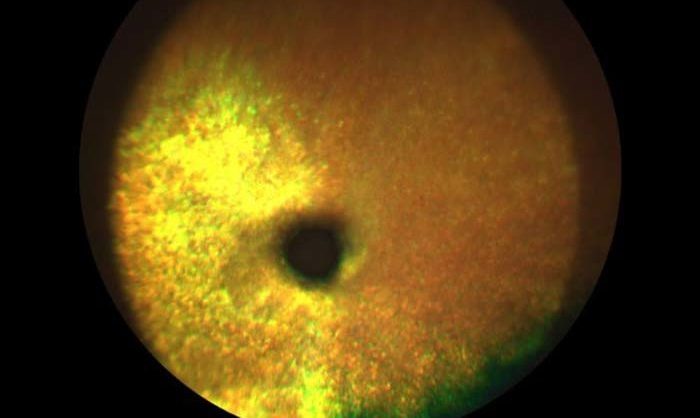

- Атрофическая или неэкссудативная форма. Это наиболее распространенный тип заболевания, который встречается в 85% всех зарегистрированных случаев. Она развивается на фоне возрастных изменений в метаболизме организма. Клинические проявления включают накопление друз под макулой, что приводит к образованию участков атрофии. Скопления могут быть классифицированы по консистенции на твердые и мягкие. При прогрессировании заболевания наблюдается постепенная потеря зрения.

- офтальмоскопия;